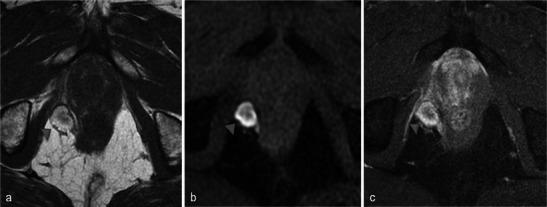

In this technique, a photosensitising agent is introduced intravenously, then activated by local laser illumination to induce tumour necrosis. Treatment efficacy is assessed by magnetic resonance imaging (MRI).

We illustrate specific post-treatment MRI aspects at early and late follow-up with pathological correlations.

• Dynamic phototherapy is a new and promising focal therapy for prostate cancer. • One-week MRI shows increased volume of the treated lobe and large, homogeneous necrosis area. • Six-month MRI shows significant changes of the prostate shape and signal. • Six-month MRI becomes "base line" appearance for further follow-up or monitoring.

在该技术中,将一种光敏剂静脉注射,然后通过局部激光照射激活以诱导肿瘤坏死。通过磁共振成像(MRI)评估治疗效果。

我们阐述了早期和晚期随访时特定的治疗后MRI表现及其与病理的相关性。

• 动态光动力疗法是一种用于前列腺癌的新型且有前景的局部治疗方法。• 一周后的MRI显示治疗叶体积增大以及大片均匀的坏死区域。• 六个月后的MRI显示前列腺形态和信号有显著变化。• 六个月后的MRI成为进一步随访或监测的“基线”表现。